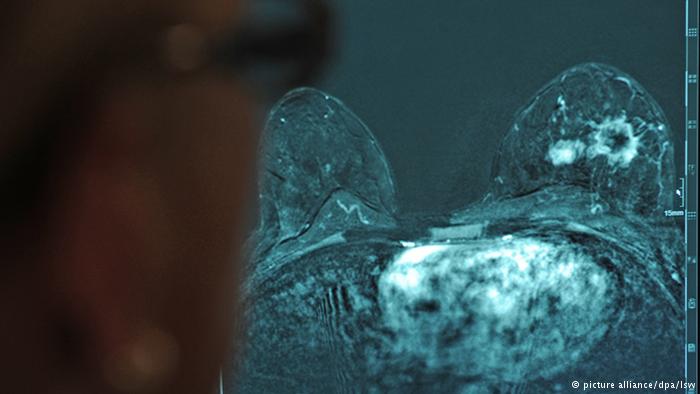

دراسة: مستويات فيتامين «د» مرتبطة بالشفاء من سرطان الثدي

كشفت دراسة أمريكية جديدة أن هناك علاقة بين ارتفاع مستويات فيتامين "د" وتحسن فرص شفاء المريضات بسرطان الثدي، إذ رصدت انخفاض مستويات هذا الفيتامين في دم المريضات وقت التشخيص.

أظهرت دراسة جديدة أن ارتفاع مستويات فيتامين "د" في الدم قد تحسن فرص شفاء مريضات سرطان الثدي كما أنها قد تجعل الأورام أقل خطورة على الحياة. وتدعم الدراسة الجديدة أبحاثاً سابقة عن ارتباط فيتامين "د" بسرطان الثدي لكنها لا تجزم بأن زيادة مستويات هذا الفيتامين في الدم يمكن أن تحسن نتائج العلاج للمصابات بسرطان الثدي. وقال المعد الرئيسي للدراسة سونغ ياو من معهد روزويل بارك كانسر في بفلو في نيويورك: "بشكل عام رصدنا انخفاضاً بنسبة 30 بالمائة في حالات الوفاة مرتبط بمستويات فيتامين (د) وقت التشخيص".